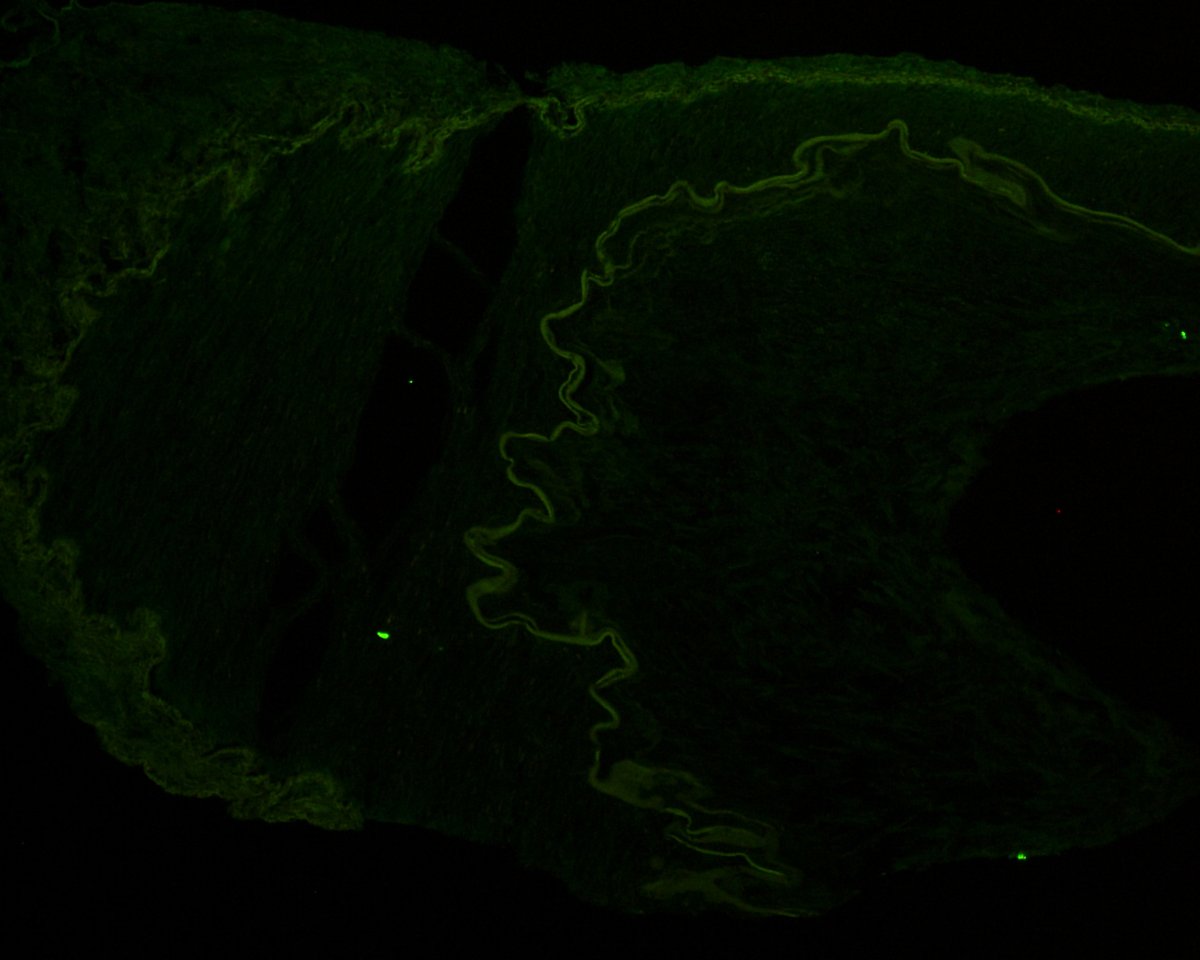

The Banff 2024 meeting report is official! Link to the article (free access) is below- now get ready for the next Banff meeting, October 5-9, 2026, in beautiful Banff, Alberta, Canada!!

authors.elsevier.com/sd/article/S16… @Renalpathsoc #renalpath